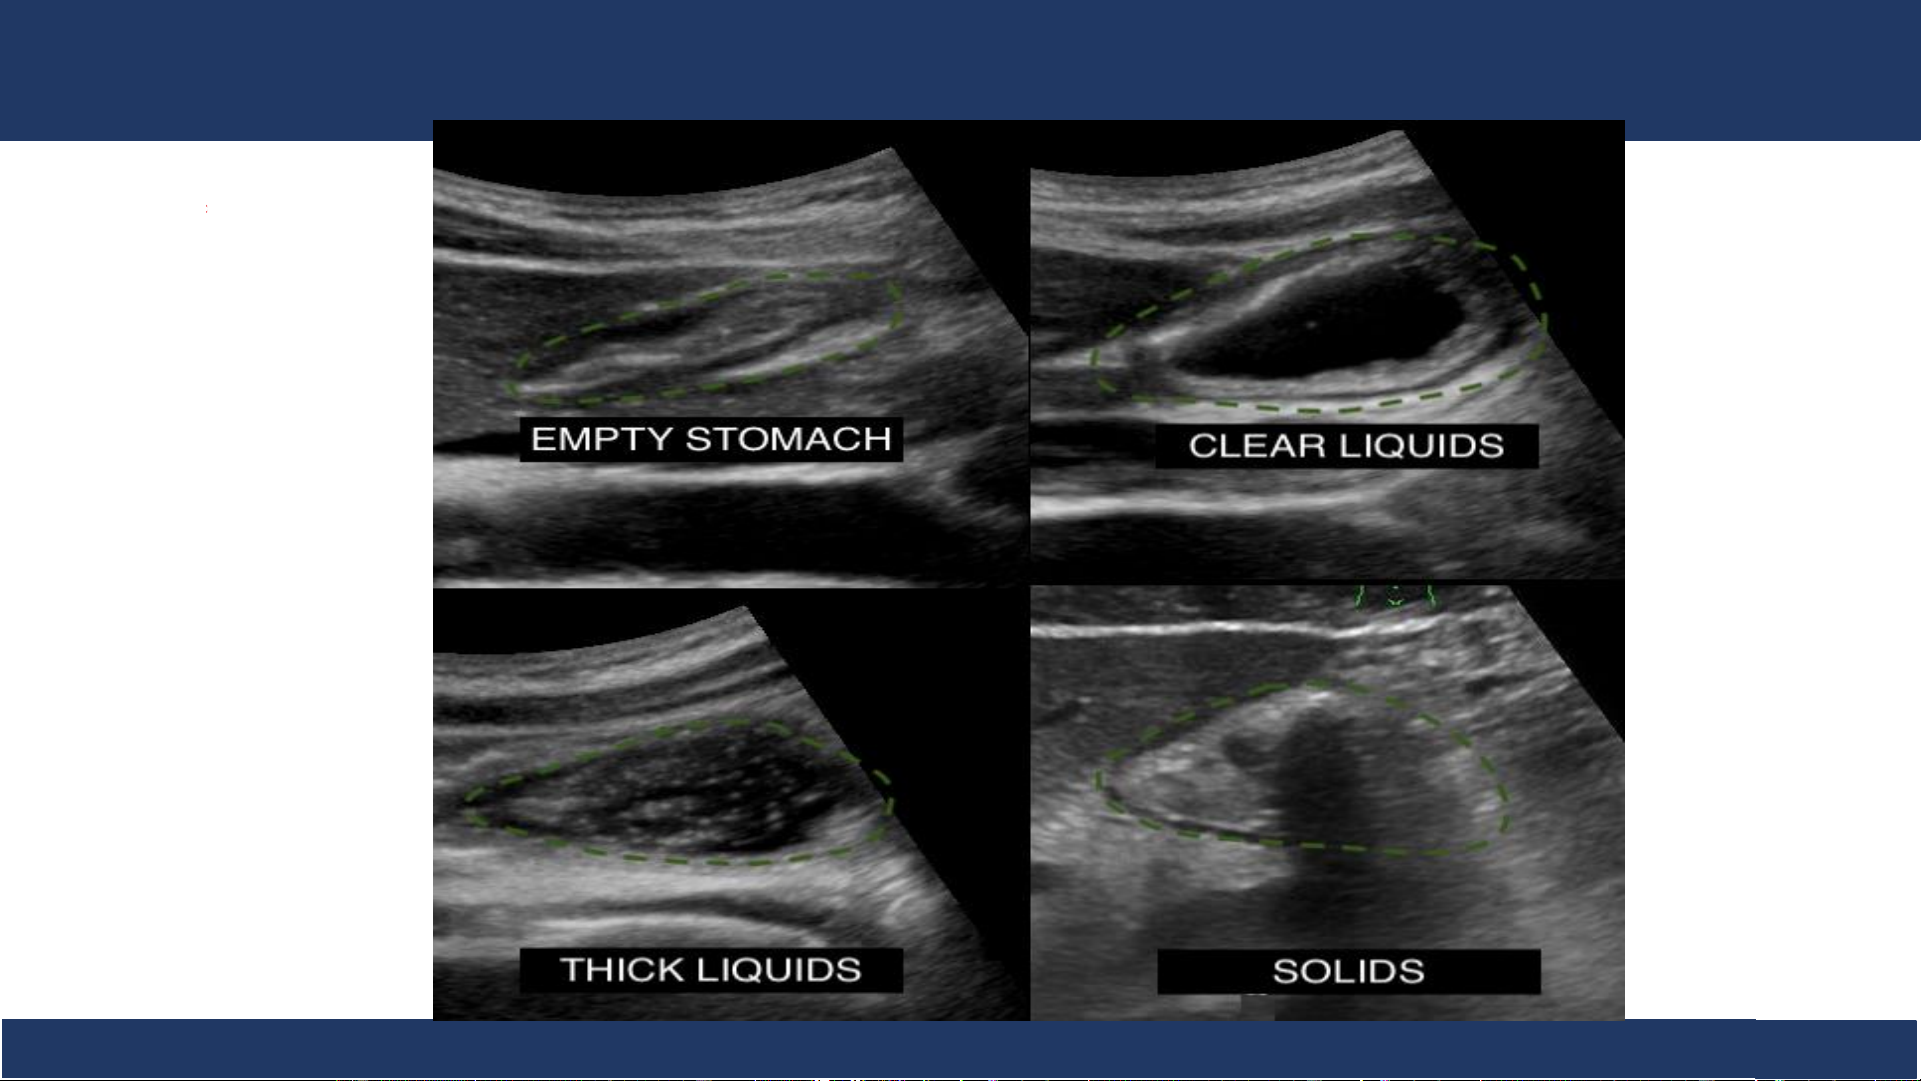

• Bề dày trung bình thành: 3-5mm • Chất chứa: thay đổi • Nhu động ruột

Siêu âm: Hình cắt ngang ống tiêu hóa, phát hiện bệnh lý. Bệnh v B iệ ộ môn n Nh Chẩ i Đồng n đoán 1